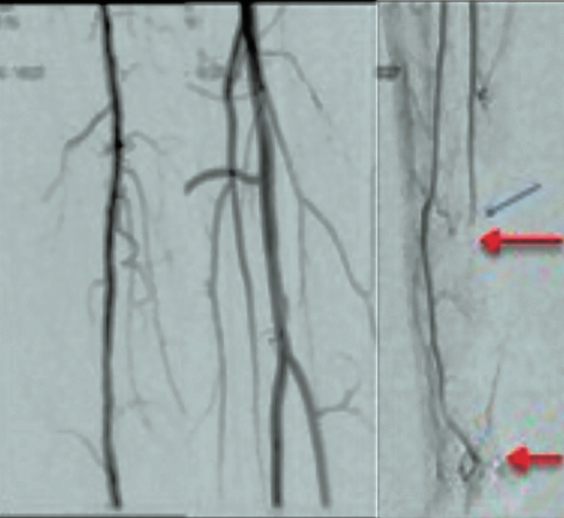

Use of the Control Mechanical Thrombectomy System in Lower-Extremity Intervention

CLD talks with George Adams, MD, MHS, MBA, FACC, FSCAI, UNC REX Healthcare, Raleigh, North Carolina.

Can you describe the problem of acute vascular thrombosis?

Thromboembolic conditions are estimated to account for approximately 1 in 4 deaths globally and are the leading cause of mortality. Ischemic heart disease and ischemic stroke comprise the major arterial thromboses, and deep vein thrombosis and pulmonary embolism comprise venous thromboembolism. Virchow’s triad is a useful concept for clinicians in understanding the contributions to vascular thrombosis. Virchow’s triad includes stasis of blood, vessel wall injury, and altered blood coagulation. Stasis of blood would include patients that have atrial fibrillation, congestive heart failure and/or cancer, or have a sedentary lifestyle (and/or long plane rides). Vessel wall injury would include patients who have trauma, infection, and/or surgery. Altered blood coagulation would include patients that have genetic deficiencies or autoimmune disorders. Age is a direct correlate to vascular thrombosis. In the 20th century, life expectancy doubled, and the world population quadrupled, so vascular thrombosis is an increasing problem.